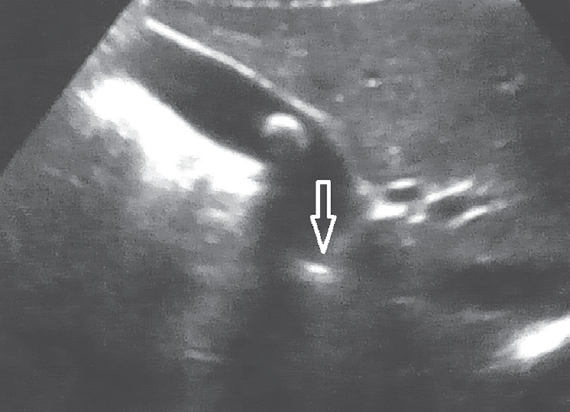

Проведенное в дооперационном периоде УЗИ гепатобилиарной системы выявило у всех пациентов с ЖКБ различные варианты деформации в области пузырного протока (рис. 4).

Рис. 4. Ультразвуковая картина деформированного пузырного протока

Fig. 4. Ultrasonic pattern of deformed cystic duct

Для сравнения во вторую группу включили 140 детей с хроническим бескаменным холециститом. Возраст пациентов был от 2 до 17 лет. В 63,6 % случаев заболевание отмечено у девочек, соответственно у мальчиков — 36,4 %. Распределение по полу и возрасту в данной группе пациентов представлено в табл. 2. Всем пациентам было выполнено УЗИ желчного пузыря. У всех отмечалось утолщение и неоднородность стенки желчного пузыря. У 15 % выявлена деформация тела желчного пузыря (рис. 2). При этом ни у одного пациента не было патологических изменений в области пузырного протока.

Рис. 2. Деформация тела желчного пузыря

Fig. 2. Gallbladder deformation